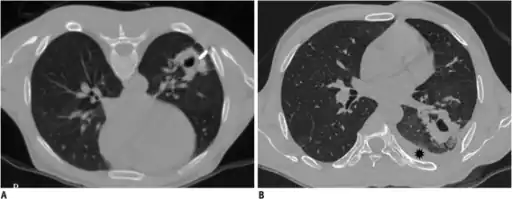

Other methods

Ultrasonography may be used to detect hemothorax and other pleural effusions. This technique is of particular use in the critical care and trauma settings as it provides rapid, reliable results at the bedside.[23] Ultrasound is more sensitive than chest x-ray in detecting hemothorax.[25] Ultrasound can cause issues in people who are morbidly obese or have subcutaneous emphysema. When CT is unavailable in the current setting or the person cannot be moved to the scan, ultrasound is used.[3]

Computed tomography (CT or CAT) scans may be useful for diagnosing retained hemothorax as this form of imaging can detect much smaller amounts of fluid than a plain chest X-ray. However, CT is less used as a primary means of diagnosis within the trauma setting, as these scans require a critically ill person to be transported to a scanner, are slower, and require the subject to remain supine.[23][26]

Ultrasound scan of the chest showing a left-sided hemothorax

CT scan of the chest showing a hemothorax caused by warfarin use